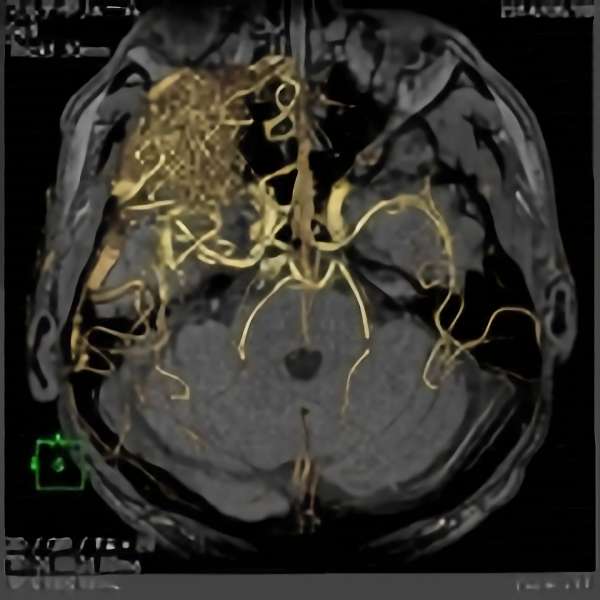

脳血管撮影

手術前

手術後